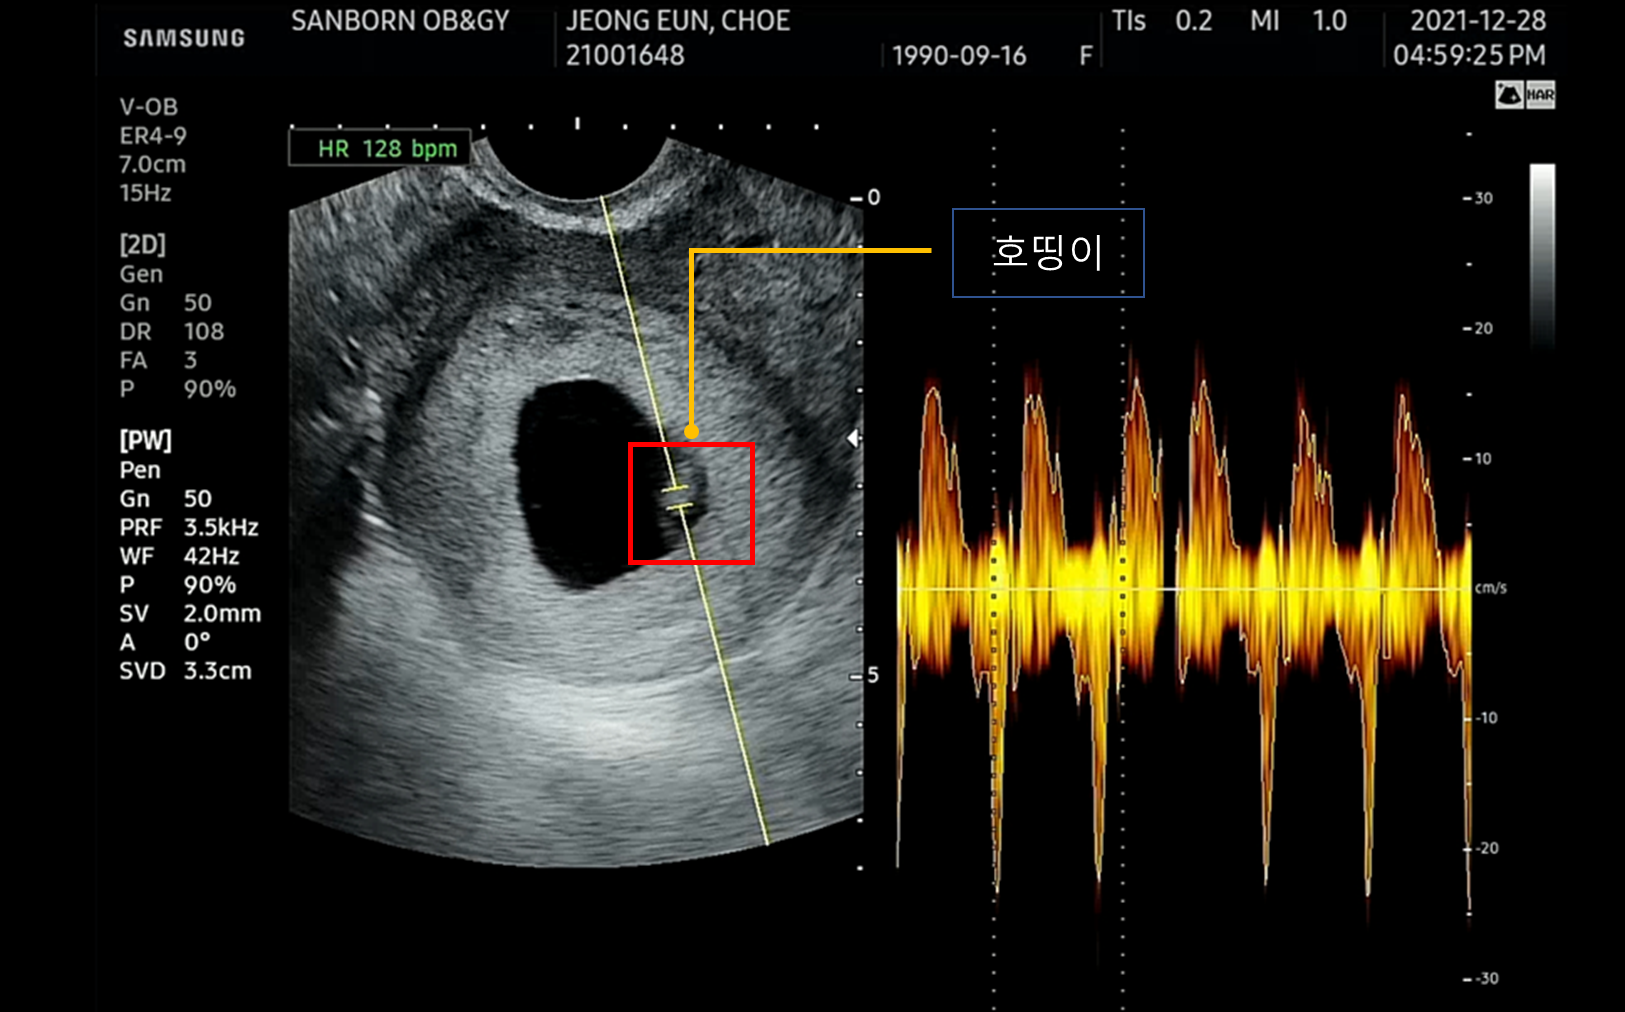

- 6주 4일차의 호띵이 심장박동 초음파 ('2021.12.28)

저기 아기집속 작은 아기가 우리 호띵이다.